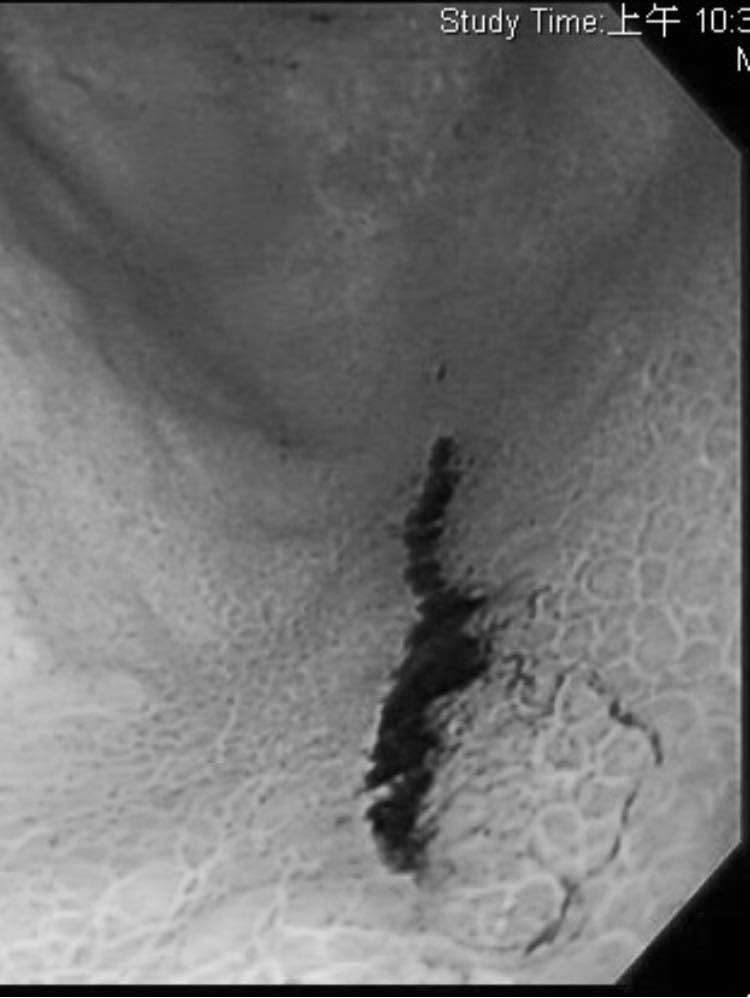

▲黑色處為出血痕跡,翻攝自臉書 (錢政弘 胃腸肝膽科醫師) ,下同。

40多歲男病患因為左上腹悶痛、最近常解出深色便便就醫,錢醫師一照胃鏡驚覺「胃裡有大大小小共5處潰瘍和糜爛,還有出血過的痕跡」,但男病患對上述5大成因卻矢口否認。男病患性格開朗也沒吃藥,「平常飲食清淡,三餐正常,不吃甜食或零食,也不喝咖啡茶或果汁,檢查也沒有幽門桿菌」。錢醫師刨根究底才得知,原來男病患近日買了一箱可樂,每晚在家喝1罐。

錢醫師解釋酸性食物別過量,建議本身有胃病或胃食道逆流的患者避開檸檬汁、柳橙汁、橘子等「比較酸」的飲料和食物,並舉例鳳梨汁、蘋果醋、蔓越莓汁等果汁的PH值皆小於4,「可樂的PH是2.3!」錢醫師判斷也許還有其他原因造成男病患胃潰瘍,「不過可以確定喝可樂會使胃潰瘍變得更嚴重,他應該是真的喝太多了。」你知道可樂比檸檬汁 (PH值3.2) 還酸嗎?